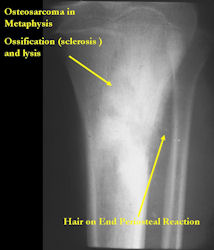

Gross Pathology: Conventional Osteosarcoma

These are examples of the gross pathology specimens of resected conventional osteosarcoma, consisting of both bony and soft tissue areas. X-rays of the specimens are included.

- Osteosarcomas are composed of ossified or non-ossified tissue

- Ossified tissue is yellow-white and hard

- Less ossified tissue is soft and less yellow

- Non-ossified tissue is tan and fleshy

- Most (95%) of conventional osteosarcomas penetrate the cortex and form a large extraosseous soft tissue mass

- The lesion permeates the marrow spaces

- Osteosarcomas usually infiltrate the marrow several centimeters away from the main tumor mass

- Skip lesions may be apparent that are separated from the main tumor by normal marrow

- Osteosarcomas may also have cartilaginous components that appear as translucent lobules, and/or fibrous components that are tan, soft to firm rubbery areas

- Osteoblastic areas are usually white to yellow, firm, hard and gritty

- The consistency of the tumor depends on the amount of osteoid deposition, cartilaginous and fibrous areas

- Foci of hemorrhage and necrosis are common

- Periosteal reactions such as the Codman’s triangle are apparent at periphery of soft tissue mass

- Osteosarcomas rarely penetrate the growth plate grossly

- Invasion of the joint is uncommon but can occur by cortical penetration, joint capsule extension, or extension along cruciate ligaments